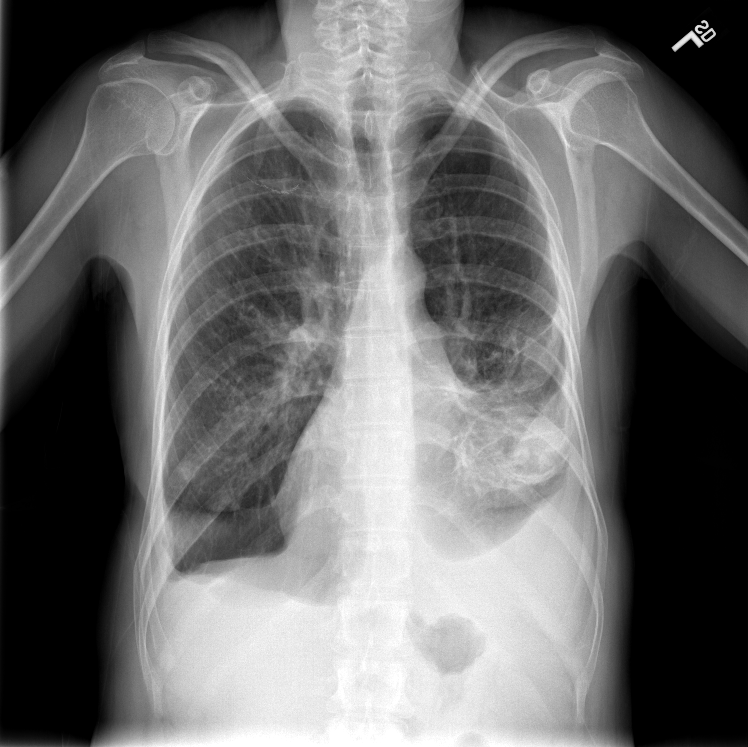

Refer to caption

(a) ”Normal”

(b) ”Bone suppressed”

(c) ”Lung field cropped”

(d) ”Combination”

Fig. 1: One example image (a) of the Indiana chest X-ray dataset from Open-I. The dataset consists of 3125 frontal and lateral images from 3125 patients. We annotated all images with up to eight findings. The pre-processed images are show in (b)-(d). (b) is the bone suppressed image, (c) is cropped to the lung field, and (d) illustrates the combination out of (b) and (c).